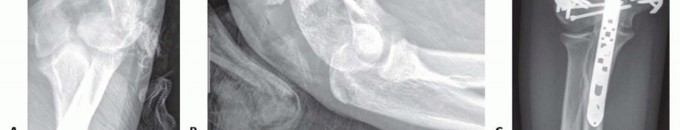

FIG 2 • A,B. A 15-year-old boy with type IIIA open distal humerus comminuted T-condylar humerus fracture. C,D. Three months following open reduction and internal fixation with olecranon osteotomy. Range of motion 0 to 140 degrees with no pain. Older children and young adolescents will often require an open approach. Comminution in the fossa may necessitate an olecranon osteotomy (FIG 2).Generally, pediatric fractures are less comminuted than adult fractures and may not require a full osteotomy.A Morrey slide approach is used in such a case where the triceps and ulnar periosteum are elevated off the ulna medially to expose the distal humerus without performing an osteotomy.3It was originally described to avoid olecranon osteotomies in cases where total elbow replacement would be a salvage operation.It can be useful in adolescents because the fractures are not as comminuted, but excellent visualization of the joint is desirable to provide anatomic reduction and restoration of elbow function. FIG 3 • A. A 13-year-old boy with a T-condylar humerus fracture with coronal split of the capitellum. B.

Open injuries should be addressed surgically within 24 hours; closed injuries may be addressed semielectively.Attention is given to the distal radius; “floating elbows,” in which both the distal humerus and distal radius and/or ulna are affected, are not uncommon. These injuries should be identified early, as they are at increased risk for compartment syndrome.The soft tissue envelope is an important consideration. Fracture blisters (see FIG 3B) can be present, which can compromise the sterility and the closure of the procedure.The vast majority of T-condylar humerus fractures require operative treatment. In younger children, a percutaneous or mini-open approach may be possible.In older children and adolescents, an open posterior approach offers direct visualization and anatomic reduction and fixation of fracture fragments.